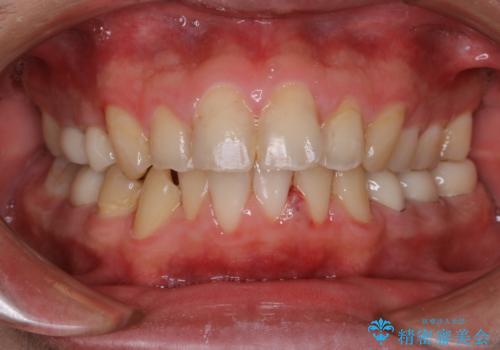

インビザライン矯正治療のスキャニング前のPMTC

- インビザラインでのスキャニング前にPMTCを希望されました。PMTC60分コースを行いました。

矯正治療前には、PMTCで歯石や汚れを取り除き、健康的な歯肉の状態にすることが大切です。PMTCでは、がたつきになどより、ご自身では取り切ることのできない細かい部分などに付着した汚れなども、専門的な機械や材料を使用してクリーニングを行います。

また、しっかりと汚れを除去することで、虫歯や歯周病などを早期発見することができます。